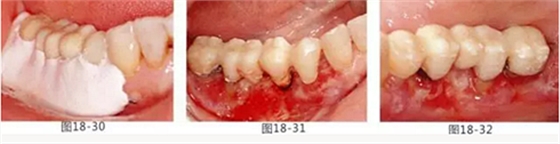

圖18-30 在頰側(cè)以及舌側(cè)涂上牙周塞治劑。然后將咬合面少許削除。

圖18-31 手術(shù)完成1周的頰側(cè)面照。

圖18-32 同部位的舌側(cè)面照。